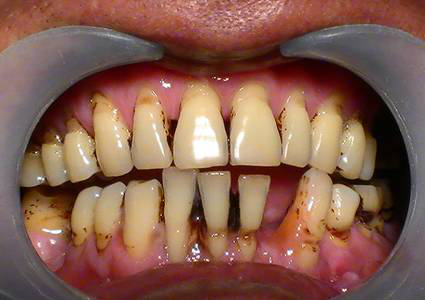

牙齦周圍菌斑、牙結(jié)石大量堆積,細(xì)菌大肆滋生刺激牙齦,引發(fā)炎癥,導(dǎo)致牙齦萎縮、牙齒松動(dòng)、移位等問題,牙齒看上去就感覺像變長(zhǎng)了。

成年人多少都患有牙周疾病,但因進(jìn)展緩慢常常忽略,發(fā)現(xiàn)問題時(shí)已到“牙周病末期”了,雖然可以通過牙周治療去除牙結(jié)石,緩解炎癥,但萎縮的牙齦卻再也找不回來了。

很多人不及時(shí)治療,都會(huì)發(fā)展成下面這種情況↓

預(yù)防:防止牙周病_好的辦法就是每半年到1年定期洗牙一次,洗牙是有效去除牙結(jié)石的唯一辦法。

治療:如果已經(jīng)患了牙齦萎縮的朋友,需要盡早進(jìn)行牙周刮治,將牙齦邊的牙結(jié)石清除干凈,雖然之前的牙齦很難救回來了,但防止它繼續(xù)萎縮下去也是非常必要的。